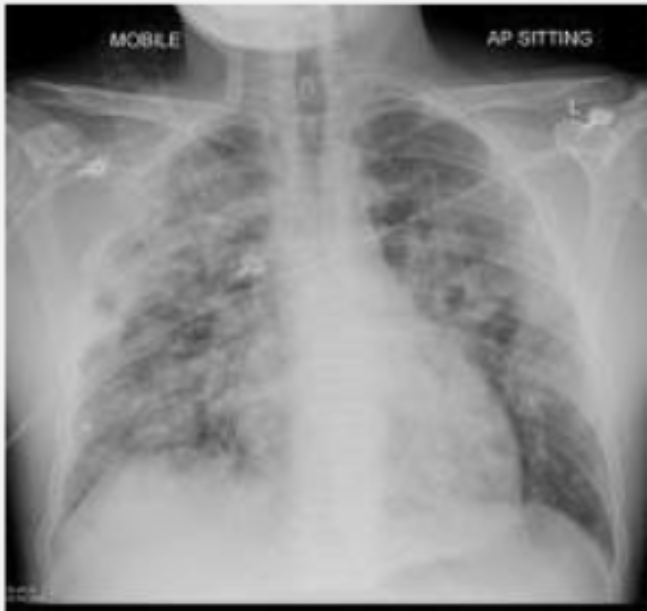

CRX of pneumonia

infection in lung

CRX of pulmonary oedema

adult respiratory distress syndrome

response to disease

lungs become stiff